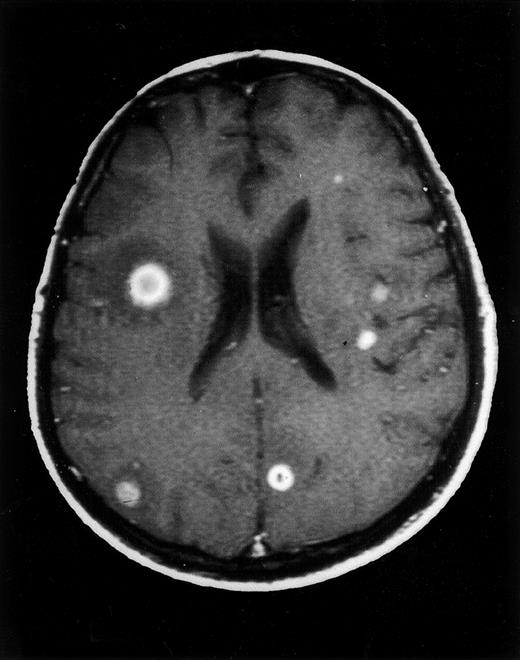

Axial contrast-enhanced T1-weighted MRI image of the brain at diagnosis.

Multiple intraparenchymal lesions are detected, some with surrounding vasogenic edema. Characteristic ring-enhancing lesions are shown at the right inferior frontal gyrus and the corticomedullary junction of the left superior frontal gyrus.

A 52-year-old man was admitted to our department with asymptomatic severe thrombocytopenia (18 × 109/L), found on a routine full blood count (FBC). Clinical examination was unremarkable. Routine blood chemical values were normal, and tumor markers were negative. Serological tests for hepatitis B and C viruses, cytomegalovirus, Epstein-Barr virus, herpes simplex virus, herpes zoster virus, and human immunodeficiency virus (HIV) were negative. The patient had no clinical or laboratory evidence of autoimmune or immunodeficiency syndromes. Findings on chest radiograph and computed tomography (CT) scans of the chest, abdomen, and pelvis were normal. A bone marrow smear revealed normal numbers of megakaryocytes in an otherwise normal bone marrow, while antiplatelet IgG and IgM antibodies were positive. Treatment was initiated with 1 mg/kg oral MP daily, and 3 days later the patient was discharged after a prompt recovery of the platelet (PTL) count (70 × 109/L). The patient was followed up at the outpatient clinic, and tapering of MP was initiated after 4 weeks of treatment, while corticosteroid-induced type 2 diabetes mellitus developed. Eight weeks later, while on 24 mg MP daily, the patient was readmitted, afebrile and with a 3-day history of fatigue and palpitation. The FBC revealed a normal hemoglobin level and white blood cell and platelet counts. A radiograph of the chest showed patchy, nodular consolidations in both lungs. MP was tapered to 16 mg every other day (and discontinued on the 14th day of hospital stay), while cotrimoxazole, ceftriaxone, clarythromycin, and fluconazole were administered. Repeat virology (including HIV) and immunological laboratory tests again excluded any underlying autoimmune or immunodeficiency syndromes. Culture specimens of blood, sputum, and urine were negative for microorganisms. A bone marrow smear was unremarkable. Microscopical examination of a stained specimen of sputum showed no acid-fast bacilli. A urine test for legionella antigen was negative. On the fifth day of hospital stay, the patient became febrile (39°C) and developed a bloodstained productive cough. A chest radiograph revealed an increase in the bilateral nodular and patchy consolidations, while a CT scan of the chest on the eighth day of hospital stay showed bilateral multifocal nodules with cavitation. Amphotericin 1.5 mg/kg IV and itraconazole 400 mg daily were initiated. On the 10th day of hospital stay, a bronchoscopy was performed and aspergillus fumigatus was isolated from bronchoalveolar lavage fluid samples. The patient showed no clinical or radiological improvement over the following days and was switched to liposomal amphotericin 5 mg/kg, while itraconazole was increased to 800 mg daily. The patient showed a slow but stable improvement and, on the 27th day of hospital stay, became afebrile. On the 30th day of hospital stay, the patient developed a brief Jacksonian-type seizure. Magnetic resonance imaging (MRI) of the brain disclosed multiple (19 in total) ring-shaped brain abscesses. T1- and T2-weighted images showed low-intensity lesions containing high-intensity areas and high-intensity lesions, respectively (Figure 1). Cerebrospinal fluid (CSF) revealed a glucose level of 64 mg/dl (serum glucose 160 mg/dl), 2 cells/mm3, 15 RBC/mm3, and 55-mg/dl protein. Microscopic examination (gram staining, acid-fast bacilli, fungi) and CSF cultures were sterile. Serum and CSF enzyme-linked immunosorbent assay antigen test for IgA, IgM, and IgG toxoplasma gondii antibodies and CSF latex agglutination tests for aspergillus and cryptococcus neoformans antigens were negative. The good condition of the patient and the small size of the intracerebral lesions (the largest, 19 mm in diameter) discouraged neurosurgeons from performing a stereotactic biopsy. Although central nervous system (CNS) toxoplasmosis was most unlikely, a 2-week trial of sulfadiazine and pyramethamine was initiated, and follow-up CT scans of the brain failed to show improvement in the lesions, ruling out CNS toxoplasmosis. We persisted with antifungal treatment, and the pulmonary lesions gradually improved while the brain lesions remained unchanged in number and size. On the 60th day of hospital stay, the patient was discharged with itraconazole 400 mg daily, in good condition and with marked improvement of pulmonary lesions but stable cerebral lesions. Over the next months, follow-up CT scans showed a slow improvement of the intracerebral lesions, while a 12-month follow-up MRI scan disclosed complete resolution of these lesions (Figure2). The presenting features and the clinical course yielded an apparent diagnosis of cerebral aspergillosis.